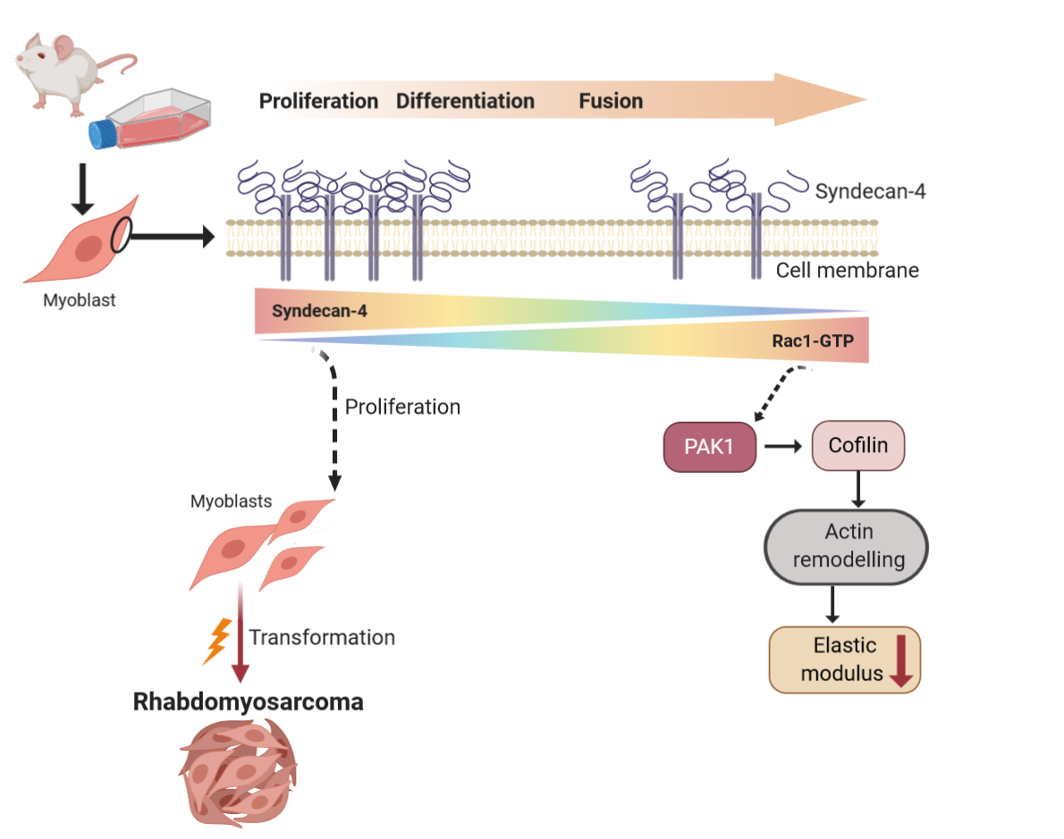

5. Oncogenesis in skeletal muscle: molecular processes and therapeutic opportunities

Rhabdomyosarcoma, the most common soft tissue sarcoma in children, arises from skeletal muscle cells that fail to differentiate terminally. As a result, instead of forming mature muscle tissue, the tumor cells grow uncontrollably. Studying how muscle cell differentiation is disrupted in RMS could help identify potential treatments that target these molecular mechanisms, either promoting normal muscle formation or preventing tumor cells from becoming more undifferentiated and cancerous.

Two subgroups of rhabdomyosarcoma, fusion-positive and fusion-negative rhabdomyosarcoma (FPRMS and FNRMS, respectively), are characterized by the presence or absence of the PAX3/7-FOXO1 fusion gene. Rhabdomyosarcomas frequently exhibit increased expression of human epidermal growth factor receptor-2 (HER2). Since HER2 is expressed in about half of rhabdomyosarcomas, the trastuzumab-mediated changes observed here may have therapeutic implications.